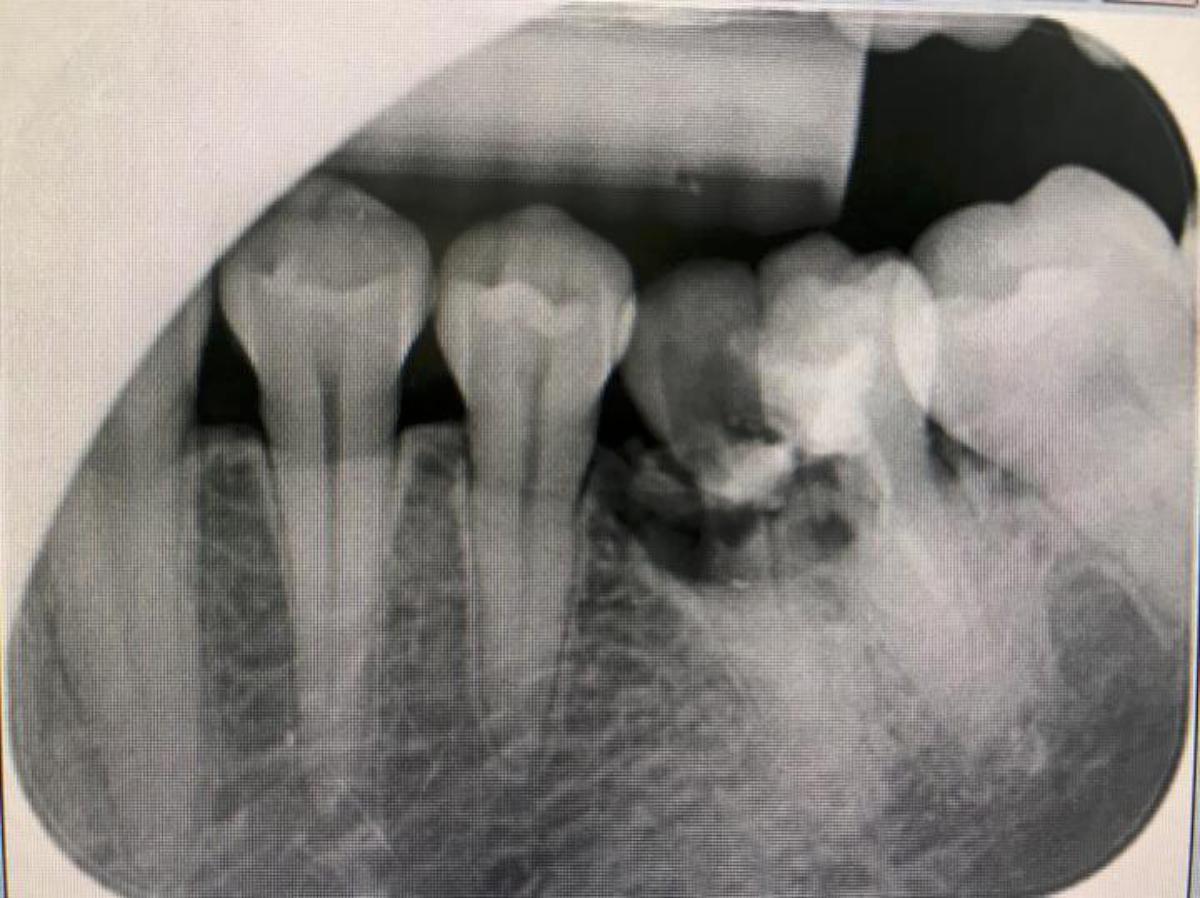

高市28歲張姓男子106年春節連假在家打電玩、吃零食,年初一食用牛軋糖後門牙受損,另名35歲周姓男子用餐時不慎咬到雞骨,造成臼齒應聲斷裂,兩人求診阮綜合醫院接受根管治療進行修補,牙科醫師陳湘蓁指出,過年應景零嘴讓人愛不釋手,造成口腔持續呈現酸性,蛀牙等問題牙齒相對脆弱恐致斷裂,根據國健署調查,年節零食攝取量比平日暴增47%,喝含糖飲料次數也多出20%,隨時進食次數增加,年後求診牙科病患激增30%。

陳湘蓁表示,提醒有補牙紀錄或牙齒結構較弱民眾,最好酌量攝取瓜子、開心果、花生等有殼食物,年長者食用牛軋糖時留意假牙可能脫落,避免掃興又傷身。想改善牙齦流血,進食後用牙刷、牙線、漱口水清潔口腔,但切忌放任不理,可能造成牙齦萎縮、齒面痠軟無力,甚至導致牙周病。

陳湘蓁呼籲,食用硬殼食物可用器具輔助,避免直接啃咬,清潔牙齒除了牙線,也可使用無酒精漱口水清除牙縫、口腔壁及舌苔,飯後立即刷牙恐造成琺瑯質受損增加蛀牙機率,建議間隔1小時再清潔牙齒,並使用牙線輔助清除殘渣再漱口。圖/阮綜合醫院提供、文/高培德